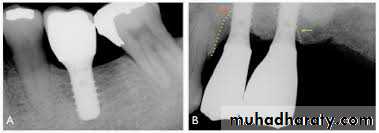

Potential Problems with Implants in Adolescent Patients

In orthodontic- prosthodontic treatment , implants serve as orthodontic anchorage units and then as abutments for prosthetic reconstructions of missing teeth in adults. In regular orthodontic treatment, the anchorage units must be placed in regions other than the alveolar bone , such as the palate. Because of the thin bone height in the palate , an endosseous implant must have small dimensions, especially in the length, so as not to perforate the nasal cavity. Another disadvantage of palatal implants is that they must be removed after the completion of orthodontic treatment with the risk of bony defects or soft tissue damageConclusions